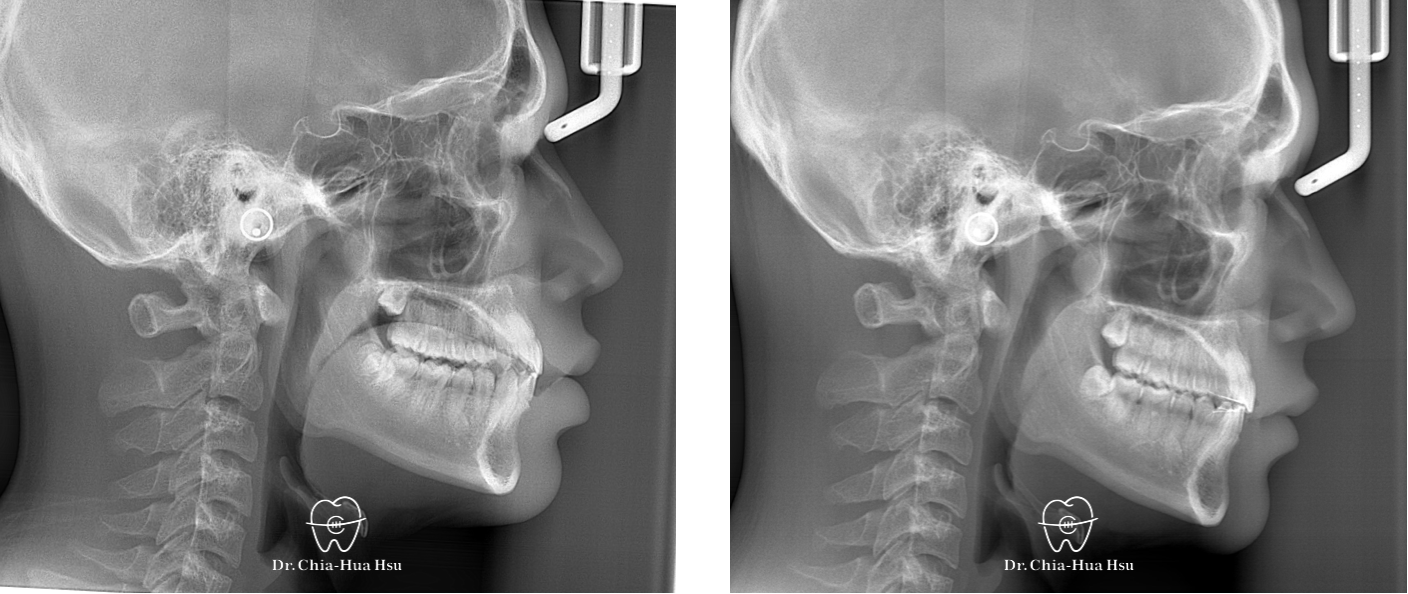

治療前

治療後